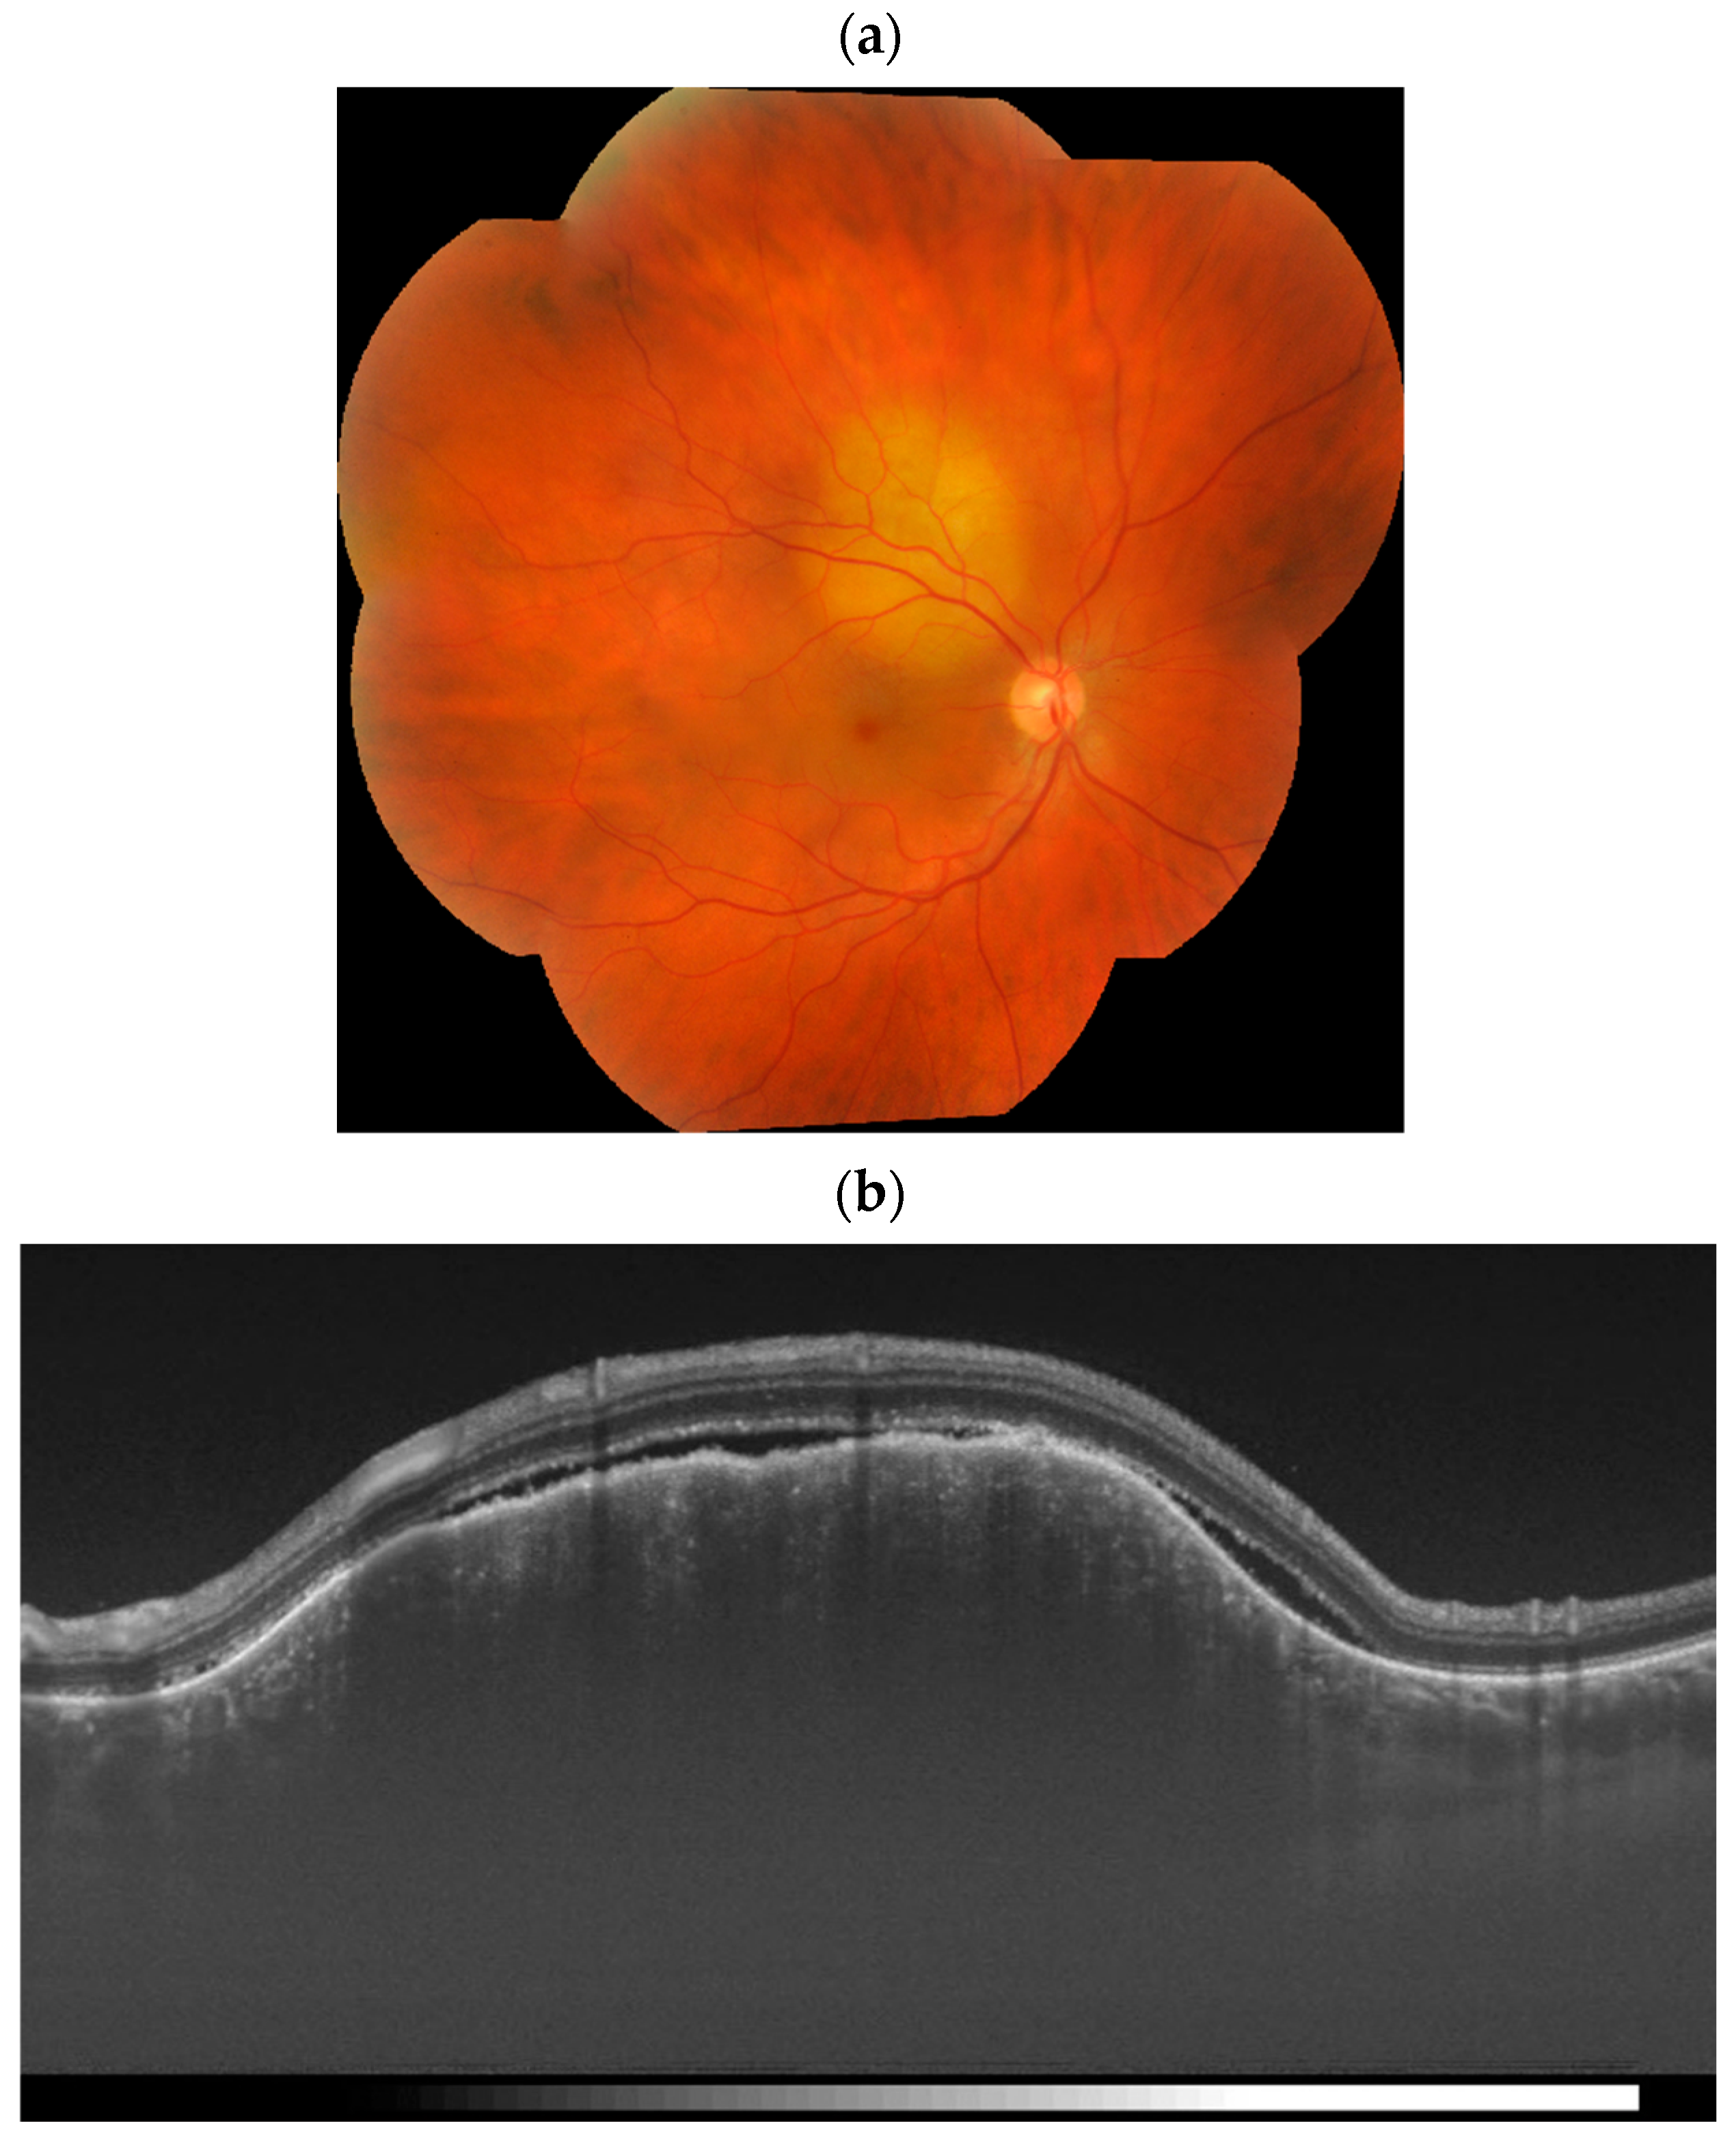

3.2. Optical Coherence Tomography

| OCT | Dome-shaped elevation of thickened RPE and retina, compression of the choriocapillaris; an irregular (“lumpy bumpy”) anterior surface; SRF; retinal pigment epithelial changes | Serous RD around and overlying the tumor; intraretinal cysts in the overlying retina, loss of retinal architecture overlying the tumor | Latticework reflective pattern; hypo-, iso-, or hyper-reflective photoreceptor loss over decalcified areas | Smooth, gradually sloping anterior tumor interface; vertical expansion of the choroid in the area of tumor with no compression of the choriocapillaris; expansion of the medium and large choroidal vessels; SRF; retinal oedema; photoreceptor loss |